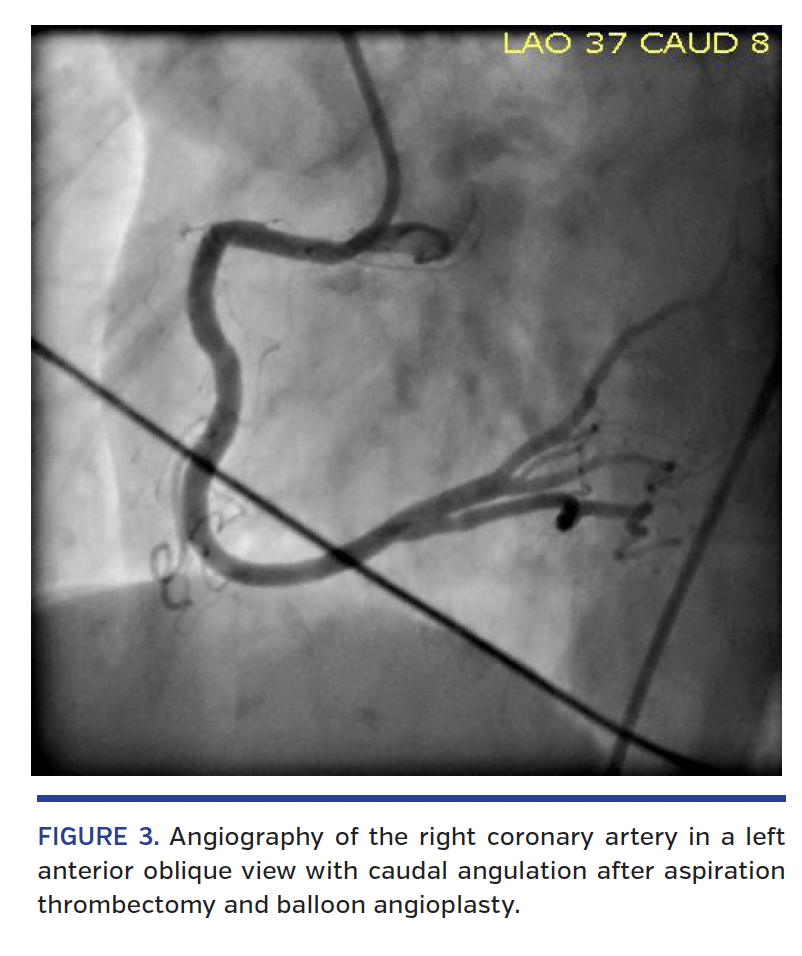

A 69-year-old woman with dementia, hypertension, hyperlipidemia, coronary artery disease, and prior percutaneous coronary intervention (PCI) of the right coronary artery (RCA) presented to the emergency department with syncope. Initial vital signs were notable for hypotension and bradycardia. Electrocardiography revealed sinus rhythm with complete atrioventricular block, a junctional escape rhythm, and 5 mm ST-segment elevations in the inferior leads, consistent with acute myocardial infarction. Loading doses of aspirin and ticagrelor were administered in the emergency department, and the patient was referred for emergent coronary angiography. Angiography of the RCA in a left anterior oblique view with cranial angulation revealed a large burden of thrombus in the proximal RCA (Figure 1) and distal embolization of the thrombus during contrast injection (Figure 2). Intravenous bivalirudin and cangrelor were immediately administered. Aspiration thrombectomy was performed with retrieval of the intact thrombus. Bradycardia and hypotension rapidly resolved. Balloon angioplasty was performed at the site of proximal RCA in-stent restenosis with improved angiographic appearance and TIMI 3 flow in the major branches at the conclusion of the case (Figure 3) (Video 1). The patient was transferred to the intensive care unit for further management.